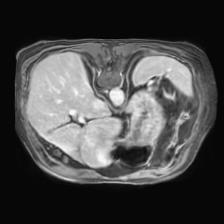

In clinical practice, well-aligned multi-modal images, such as Magnetic Resonance (MR) and Computed Tomography (CT), together can provide complementary information for image-guided therapies. Multi-modal image registration is essential for the accurate alignment of these multi-modal images. However, it remains a very challenging task due to complicated and unknown spatial correspondence between different modalities. In this paper, we propose a novel translation-based unsupervised deformable image registration approach to convert the multi-modal registration problem to a mono-modal one. Specifically, our approach incorporates a discriminator-free translation network to facilitate the training of the registration network and a patchwise contrastive loss to encourage the translation network to preserve object shapes. Furthermore, we propose to replace an adversarial loss, that is widely used in previous multi-modal image registration methods, with a pixel loss in order to integrate the output of translation into the target modality. This leads to an unsupervised method requiring no ground-truth deformation or pairs of aligned images for training. We evaluate four variants of our approach on the public Learn2Reg 2021 datasets \cite{hering2021learn2reg}. The experimental results demonstrate that the proposed architecture achieves state-of-the-art performance. Our code is available at https://github.com/heyblackC/DFMIR.